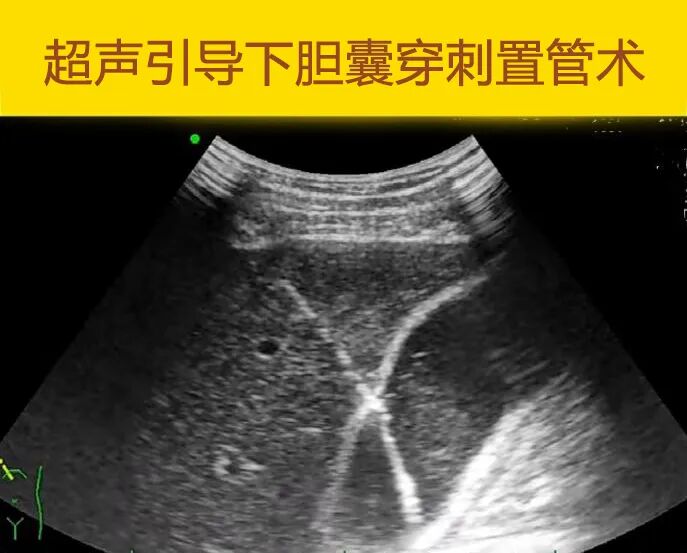

近日87岁的杨爷爷突然右上腹疼痛难忍,CT显示:胆囊炎合并胆囊结石。胆囊体积大、水肿明显,随时可能有胆囊坏疽、穿孔的危险。普外科张文副主任医师充分评估,考虑杨爷爷体质较差还并发了脑梗塞,现在手术风险较高,但通过保守治疗又难以控制感染,于是与他的家属沟通后,及时进行了超声引导下胆囊穿刺置管引流,住院1周便顺利出院了。

一、什么是超声引导下

胆囊穿刺置管引流术?